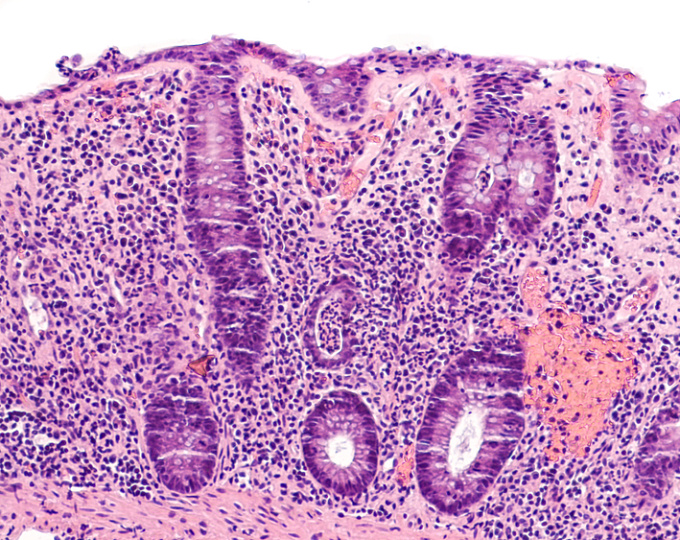

Участниками исследования являлись 54 591 пациентов с воспалительным заболеванием кишечника, диагностированным в период с 1990 по 2016 год, у которых периодически выполняли биопсию из подвздошной и толстой кишки.

В качестве основной конечной точки исследователи рассматривали переломы в течение 12 месяцев после гистологического воспаления в сравнении с гистологической ремиссией.